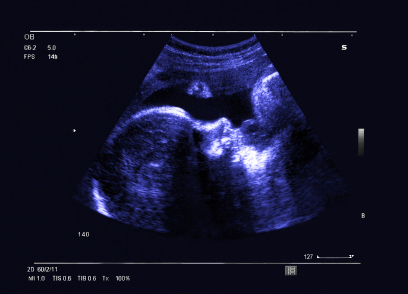

Ultrasound continues to show its utility in a variety of clinical areas around the world where radiologic resources are few.

Researchers in a recent study described the success of an intensive training program for Zambian midwives to improve their ultrasound acquisition skills when imaging pregnant women. This included improvements in competence and image quality. Read what else the researchers found in this edition’s featured story.